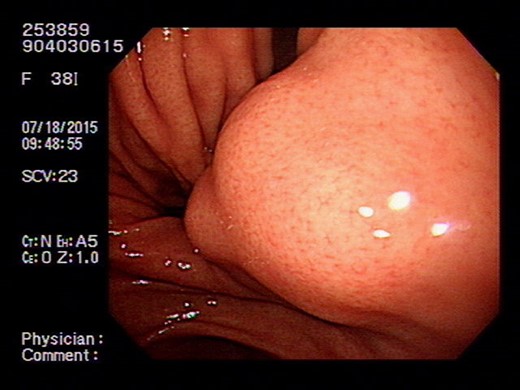

Endoscope showing intraluminal tumor with normal mucosal covering.

This is a 38-year-old female without any underline disease who came to our out-patient department due to a 2-month history of intermittent abdominal fullness and distension sensations. At first, she visited our gastroenterologist where medications promoting bowel motilities were prescribed but in vain. To further assess her condition, endoscopic ultrasonography was arranged which revealed a hypoechoic tumor with a diameter of 21.3 mm arising from the fourth layer of gastric wall. (Figs 1 and 2) An endoscopic biopsy was performed but reported negative findings due to failure in acquiring submucosal specimens on that biopsy. Based on epidemiology, gastrointestinal stromal tumor was suspected. Computed tomography was then arranged (Fig. 3) which revealed a submucosal tumor with heterogenous enhancement posterior wall of gastric antrum. No other lesion was found during that examination. Under such findings, she was then referred to a gastrointestinal surgeon for further surgical intervention.